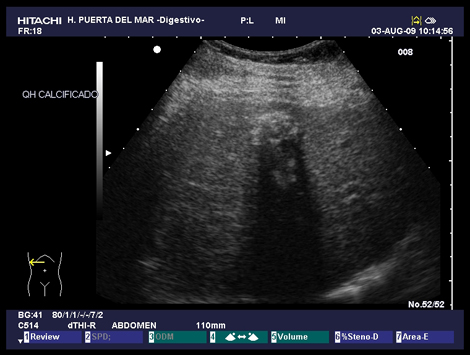

Atlas hígado

2.1. Quistes